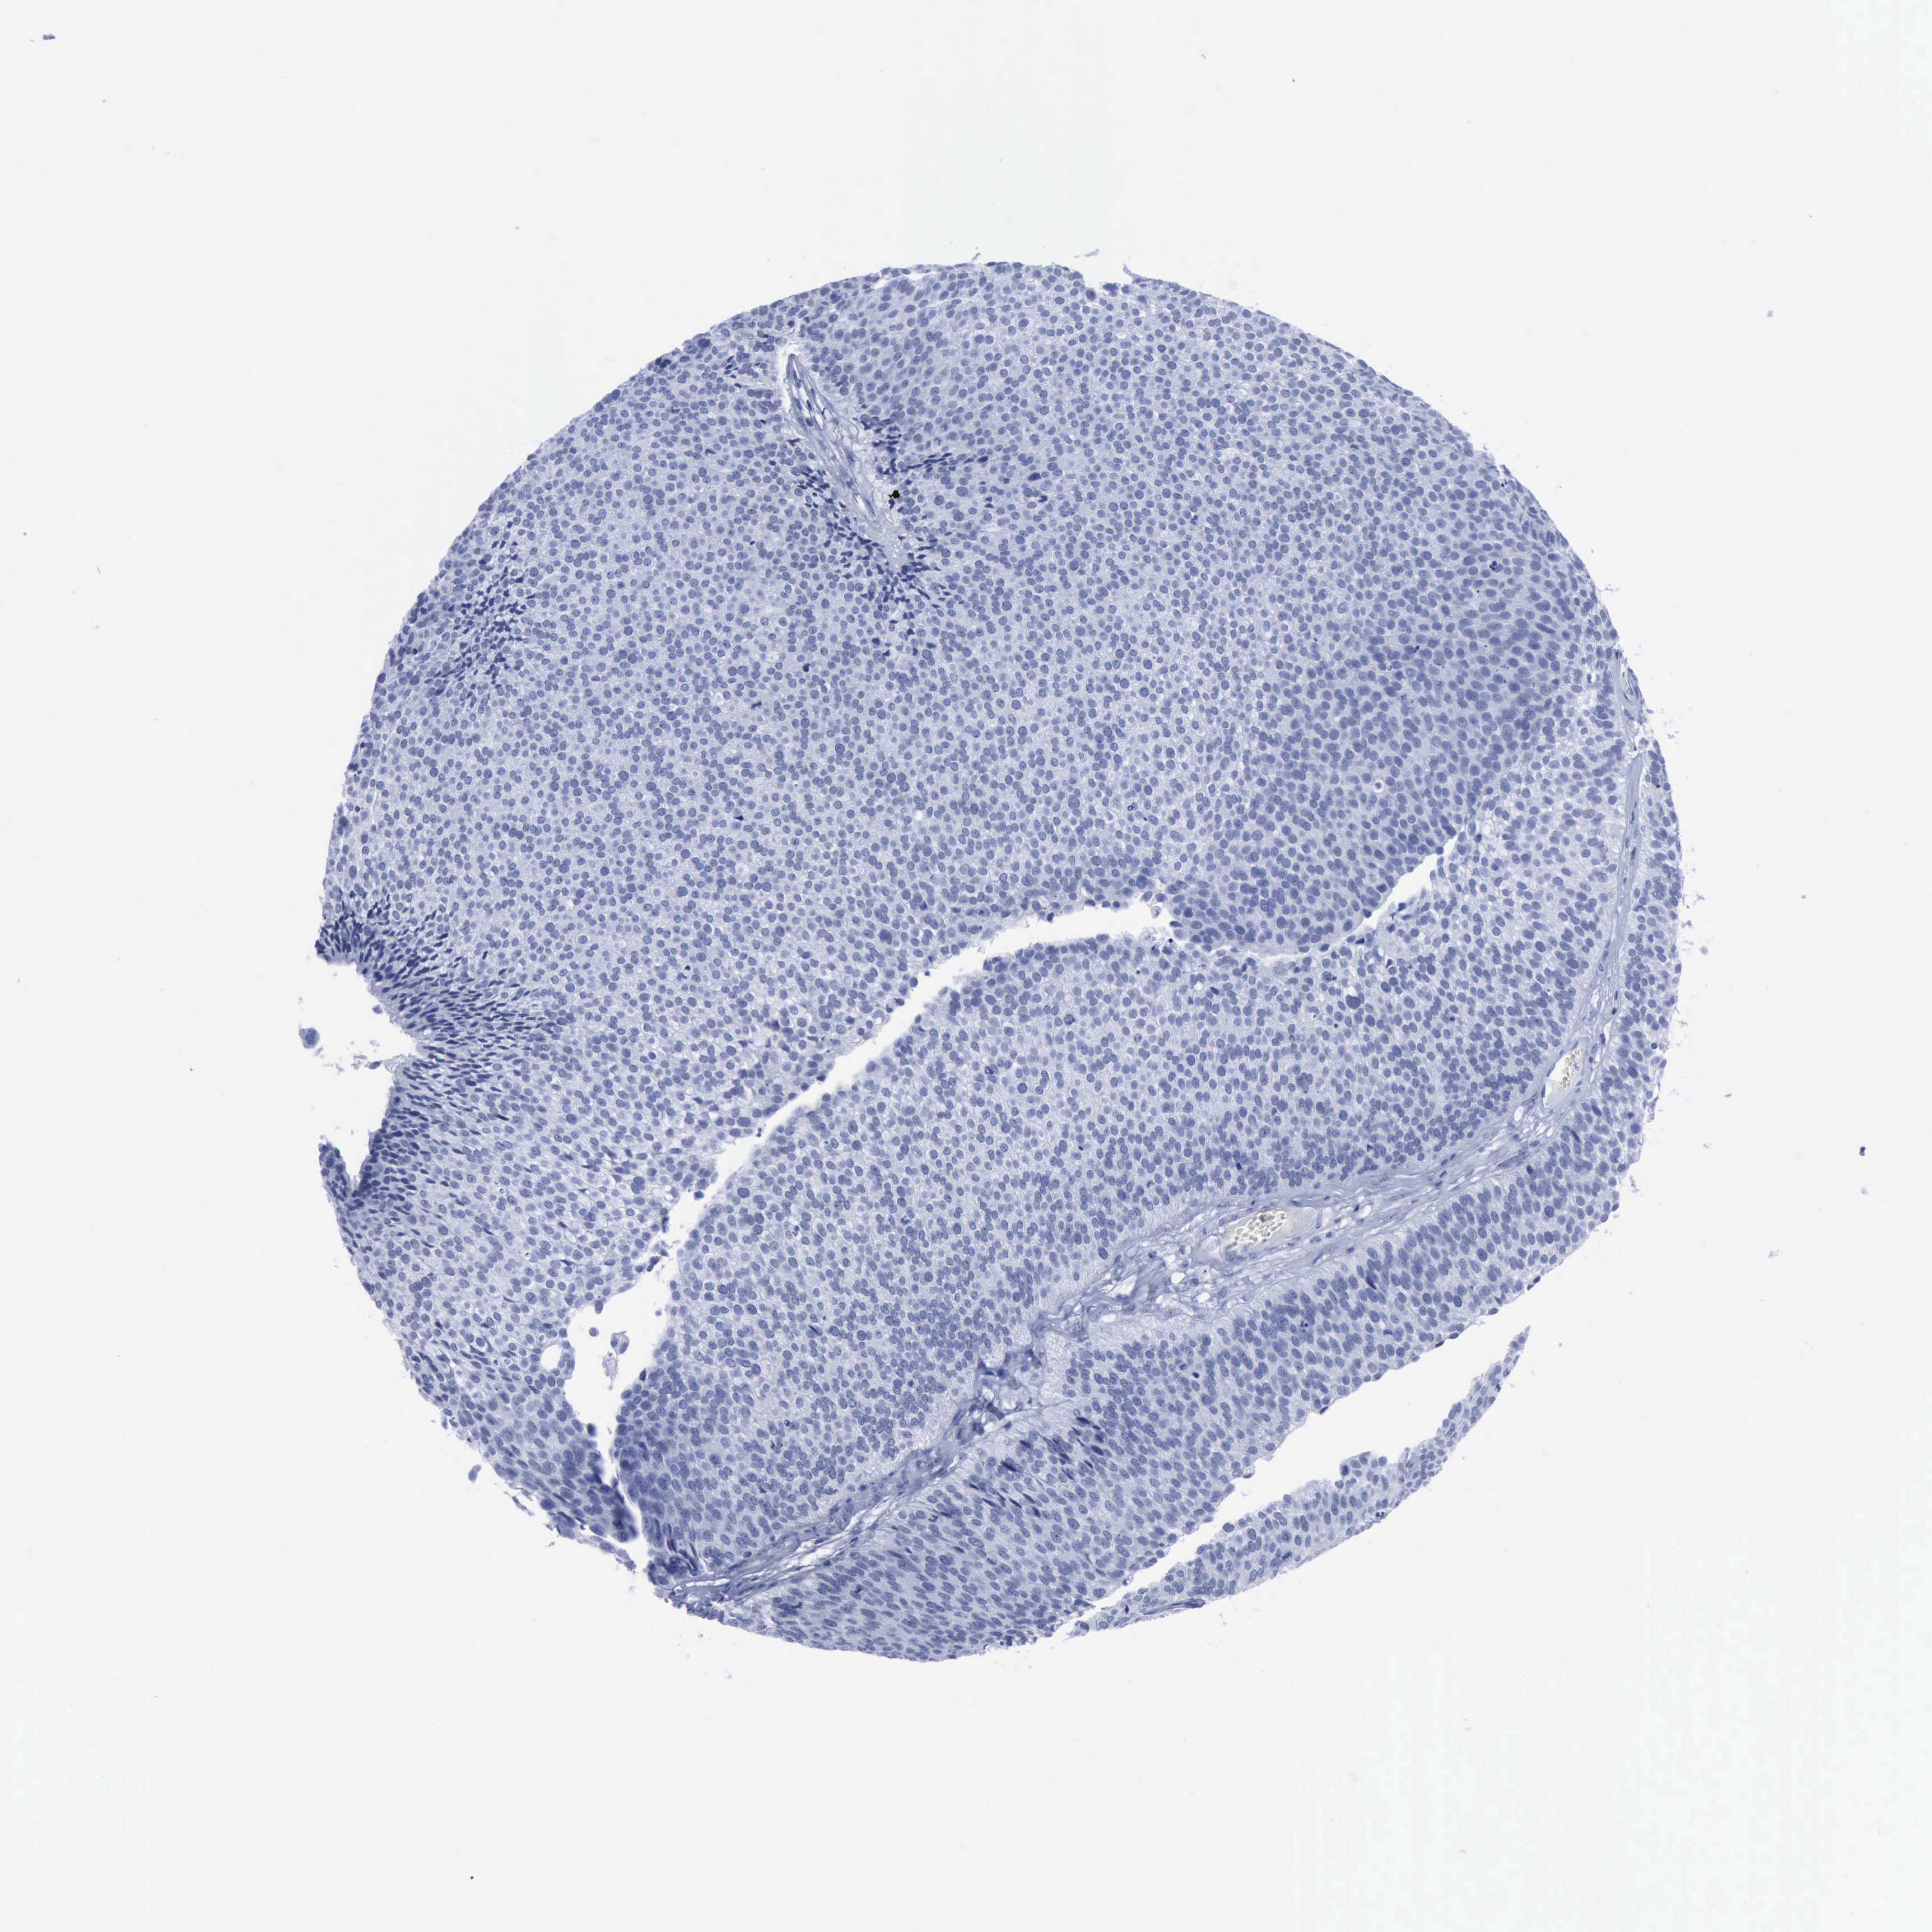

UROTHELIAL CANCER - Protein expressioni

A mouse-over function shows sample information and annotation data. Click on an image to view it in a full screen mode. Samples can be filtered based on level of antibody staining by selecting one or several of the following categories: high, medium, low and not detected. The assay and annotation is described here.

Antibody stainingi

Antibody staining in the annotated cell types in the current human tissue is reported as not detected, low, medium, or high, based on conventional immunohistochemistry profiling in selected tissues. This score is based on the combination of the staining intensity and fraction of stained cells.

Each image is clickable and will lead to virtual microscopy that enables deeper exploration of all samples and also displays staining intensity scores, fraction scores and subcellular localization as well as patient and tissue information for each sample.

Antibody CAB001995

Urothelial carcinoma, Low grade

Adenocarcinoma, NOS